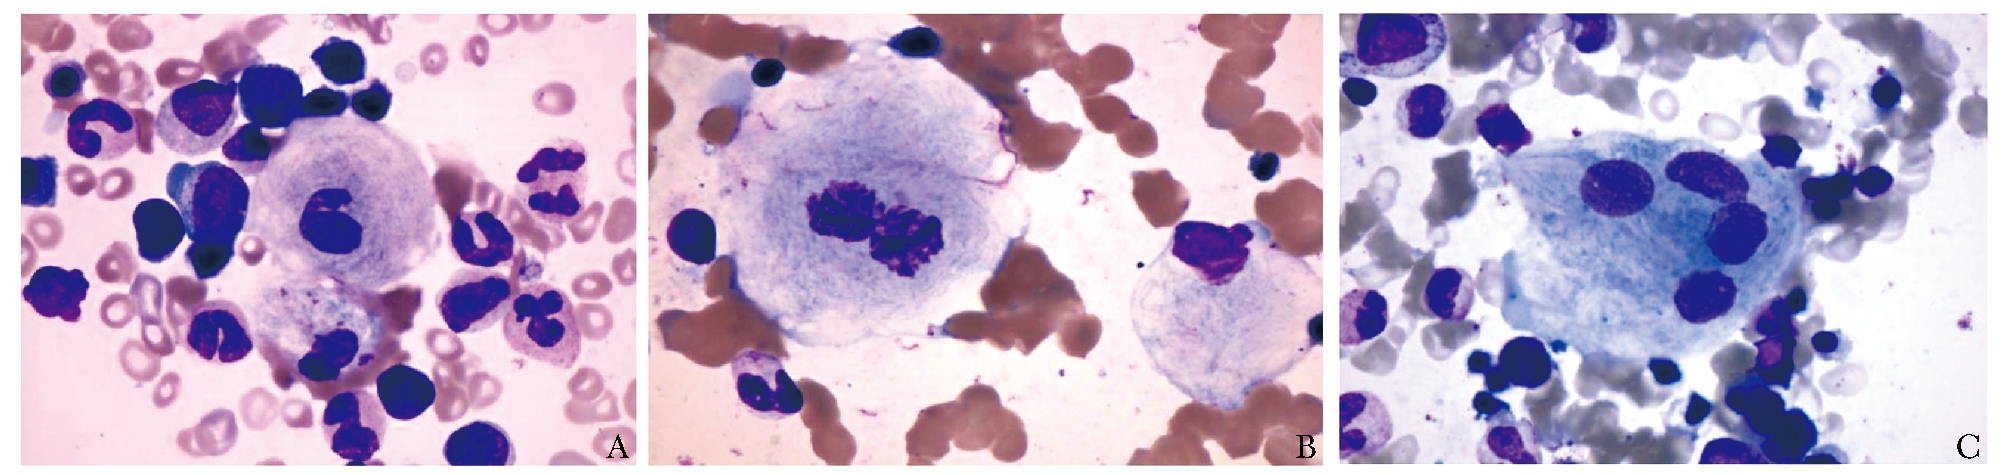

骨髓中可发现戈谢细胞,胞体大或巨大,核小,有时可见核畸形、双核及多核,染色质致密;胞浆量丰富,呈灰蓝色“洋葱皮”样排列(图1)。戈谢细胞酸性磷酸酶活性升高,必要时可进行酸性磷酸酶染色。戈谢细胞亦可见于一些血液系统疾病及感染性疾病,此时称为“类戈谢细胞”,在慢性粒细胞白血病、地中海贫血、骨髓增生异常综合征、多发性骨髓瘤、华氏巨球蛋白血症、霍奇金淋巴瘤、其他淋巴瘤伴单克隆免疫球蛋白血症甚至非典型分枝杆菌感染中均可能出现这种“类戈谢细胞”[1]。因此,当骨髓中存在戈谢细胞时,虽应高度怀疑GD,但需进一步行GBA活性测定以确诊。

图 1 骨髓戈谢细胞特征

A.巨大细胞伴核畸形;B.双核戈谢细胞;C.多核戈谢细胞